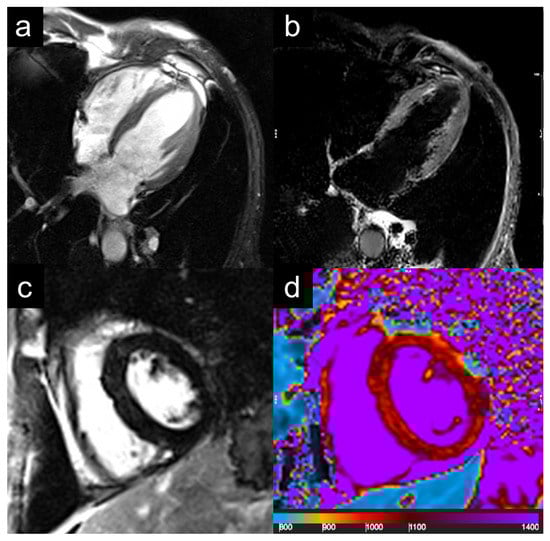

2. Case Description

3. Diagnostic Assessment